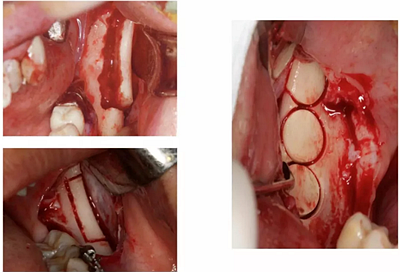

10、骨環(huán)植骨

要點(diǎn):骨環(huán)技術(shù)是解決種植垂直骨量不足并同期植入種植體的一項(xiàng)特殊技術(shù)。本操作練習(xí)骨環(huán)技術(shù)的操作步驟,在頦部取環(huán)形骨移植物修復(fù)上前牙垂直骨量不足。